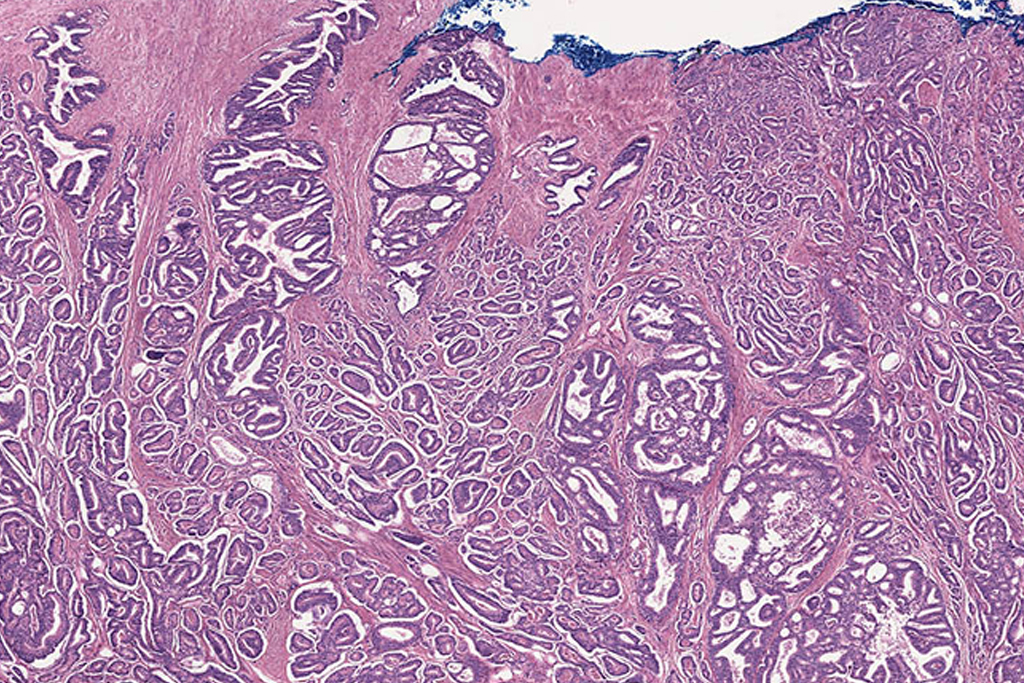

Prostate cancer is a complex disease that can only be understood by interrogating the regulatory elements among genes and proteins. In this paper we inferred a prostate cancer Gene Regulatory Network (GRN) from a gene expression data set of patient RNA-seq profiles obtained from The Cancer Genome Atlas (TCGA) database. Our network-based analysis provides a practical systems biology approach for revealing large-scale interactions of prostate cancer. This allows a close interpretation of biological activities in terms of the hallmarks of cancer. Daniel Moore, Ricardo de Matos Simoes, Matthias Dehmer, Frank Emmert-Streib Curr Genomics. 2019 Jan;20(1):38-48.